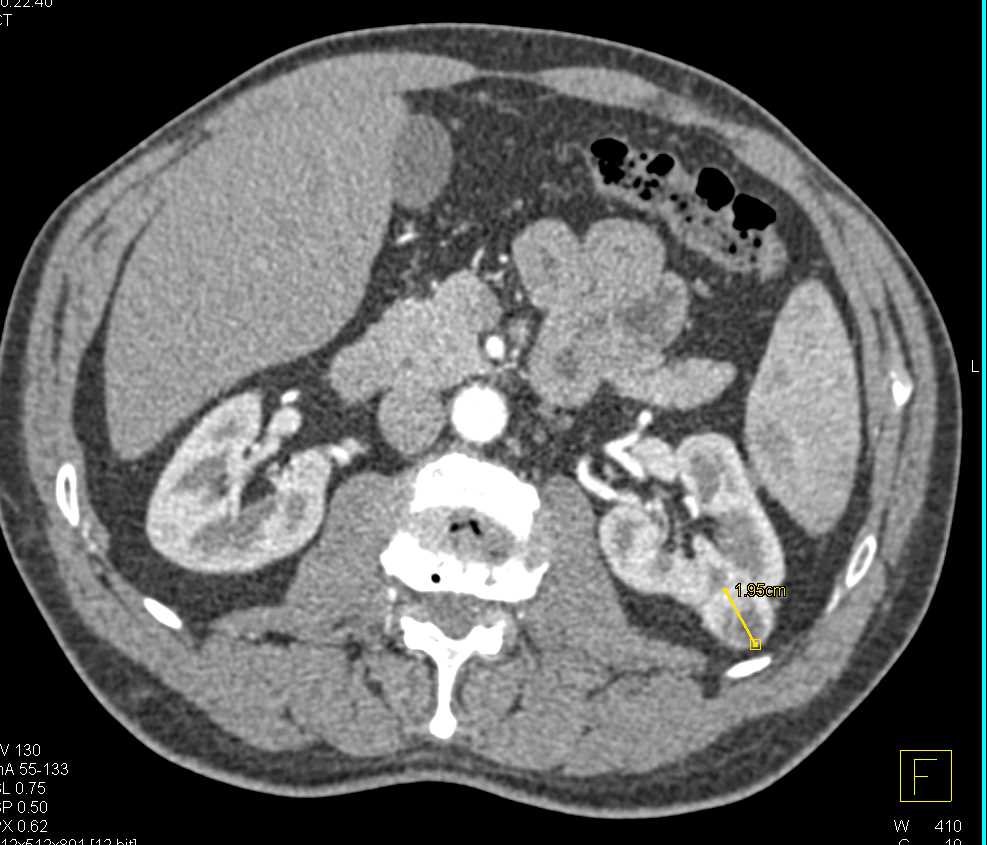

Metastatic Renal Cell Carcinoma to the Pancreas and Bone